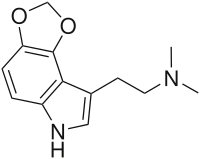

| 4,5-MDO-DMT | artificial | 4,5-(OCH2O) | CH3 | CH3 | 2-(2H,6H-[1,3]Dioxolo[4,5-e]indol-8-yl)-N,N-dimethylethan-1-amine | 81249-30-1 |

| 4,5-MDO-DiPT | artificial | 4,5-(OCH2O) | CH(CH3)2 | CH(CH3)2 | N-[2-(2H,6H-[1,3]Dioxolo[4,5-e]indol-8-yl)ethyl]-N-(propan-2-yl)propan-2-amine | 82173-82-8 |